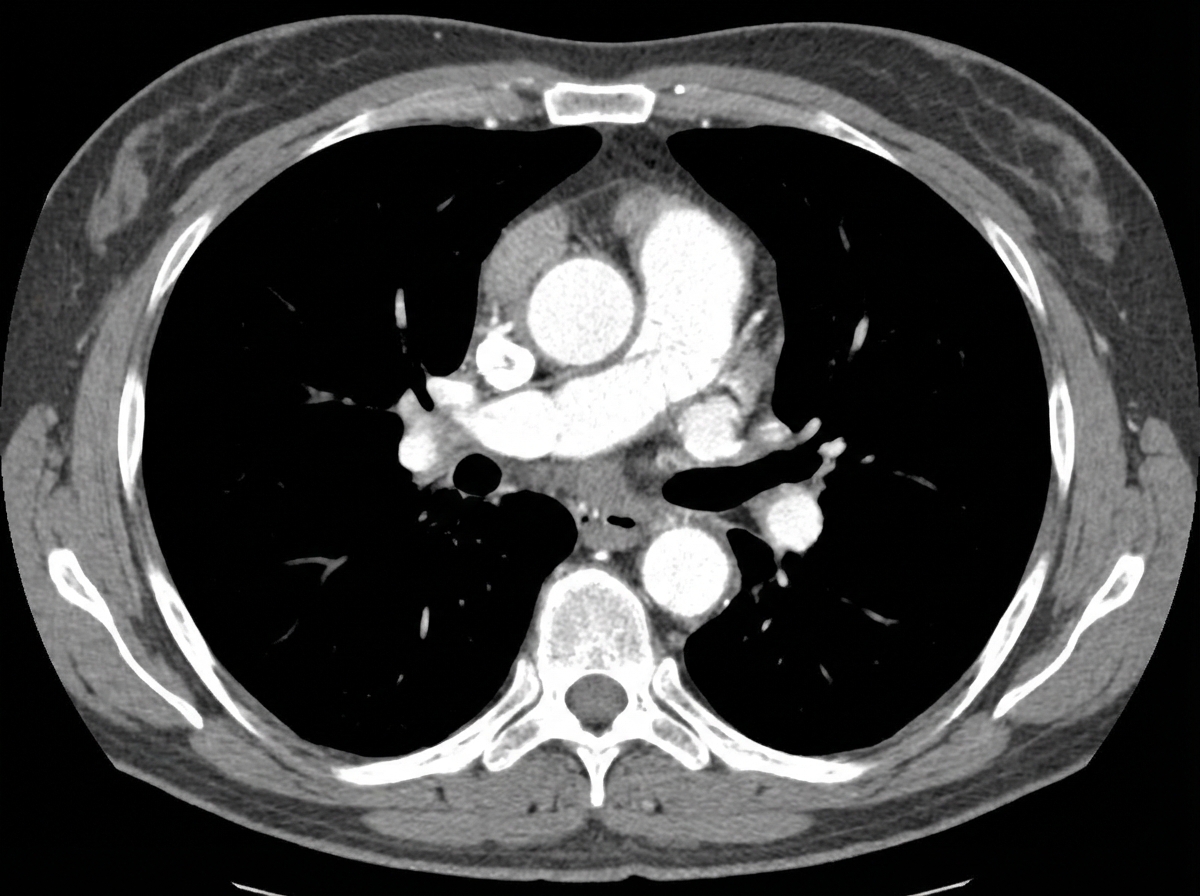

A 50-year-old male presented to the emergency department with a blood pressure of 160/100 mmHg and a heart rate of 120 bpm. A CECT scan was performed, and the image is provided. What is the management of the condition shown?

Explanation: ***Surgical repair*** - **Type A aortic dissection** (involving ascending aorta) requires **emergency surgical repair** to prevent fatal complications like **cardiac tamponade** or **aortic rupture**. - The elevated blood pressure (160/100 mmHg) and tachycardia (120 bpm) are consistent with **acute aortic dissection**, making immediate surgical intervention life-saving. *Low molecular weight heparin* - **Anticoagulation is contraindicated** in aortic dissection as it increases the risk of **extension of dissection** and **hemorrhage**. - LMWH would worsen the **intramural bleeding** and potentially lead to **fatal rupture** of the aortic wall. *Beta blocker medication* - While **beta blockers** are used in **Type B aortic dissection** (descending aorta only) for **blood pressure control**, they are insufficient for Type A dissection. - **Type A dissection** requires surgical intervention regardless of medical management due to high mortality risk without surgery. *Vitamin K inhibitors* - **Warfarin and other vitamin K antagonists** are absolutely contraindicated in acute aortic dissection due to **bleeding risk**. - These medications would promote **hemorrhage into the dissection plane** and increase the likelihood of **aortic rupture** and death.